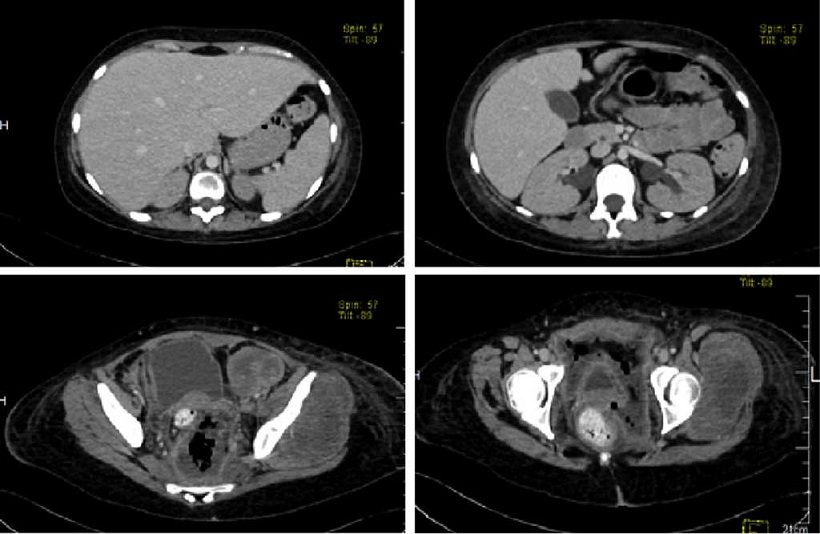

Aunque in vitro no se observaban pautas claras de la presencia tumoral, al inocularse en ratones mostraron patrones característicos de la enfermedad en humanos.